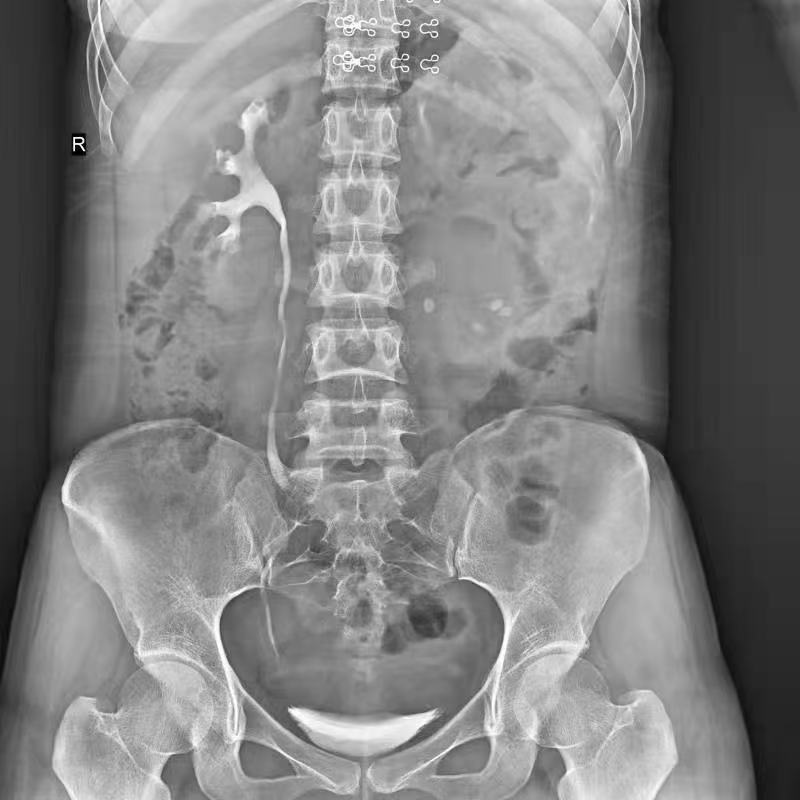

●呈現全下肢或全脊柱圖像

●在脊柱及下肢畸形矯正手術治療中,為術前方案制定和術后復查提供精準測量

●有效解決傳統X光片不能一次成像問題,為患者提供更加優質的醫療服務